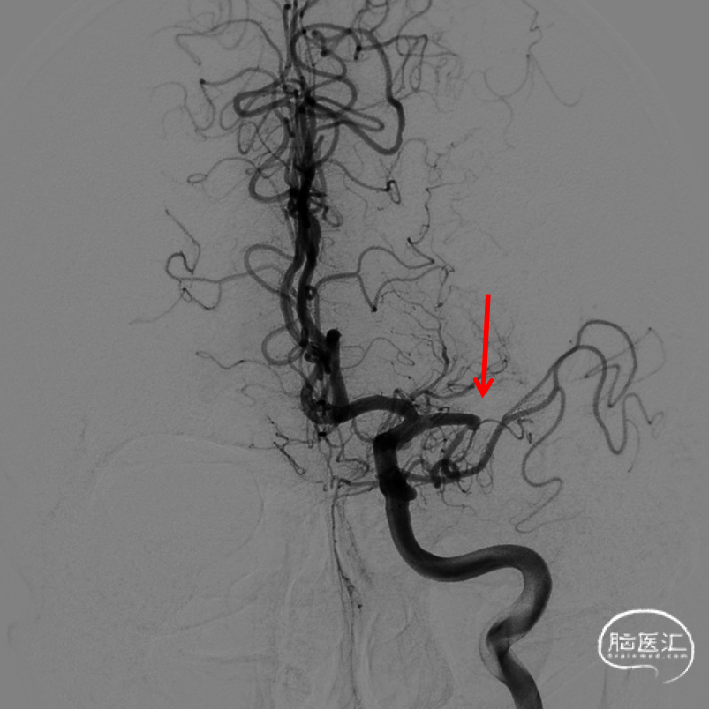

DSA

1、急性脑梗死。2、左侧大脑中动脉M1段闭塞。

ICAS合并血栓?

夹层合并血栓?

栓塞?

首过效应(+)

心玮 4-40取栓支架释放后,支架释放效应(+)